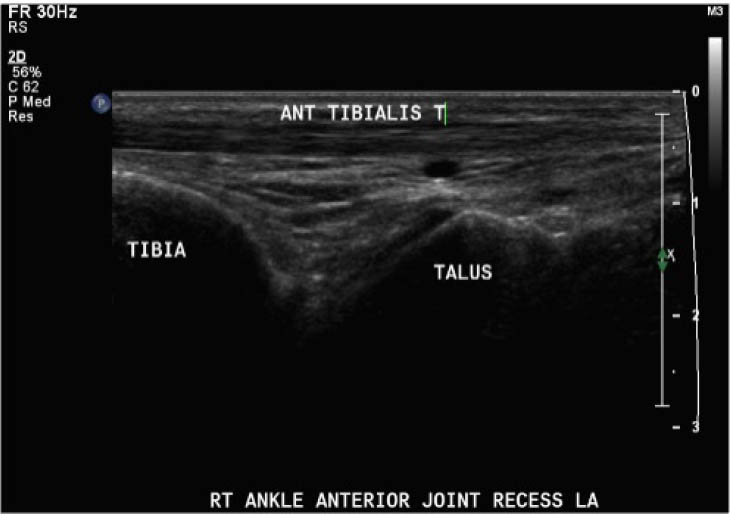

The study procedure consisted of a POCUS performed by a physiotherapist and a sonographer. The POCUS scanning procedure is presented in Appendix 1. The POCUS scans were performed in the haemophilia ambulatory clinic at patient presentation, one-week follow up, and two-week follow-up. The order of assessment was based on clinician availability. The sonographer was allowed to add additional images to the imaging protocol given their area of expertise, but the physiotherapist was instructed to acquire the images according to the scanning procedure. Ambiguous results were referred to the diagnostic imaging department for further formal investigation. Both the physiotherapist and the sonographer were blinded to each other's findings and to the results of previous scans. Methods of blinding included the use of a private clinic room and each clinician performing their assessment and documentation independently. Case report forms were placed in a sealed envelope. POCUS images were saved on the hard drive of the POCUS machine (GE Logiq) using an anonymous participant identification number.

Outcomes were assessed at presentation, one-week follow-up, and two-week follow up, resulting in a three-week study period. For the primary objective, the outcome of interest was the binary decision on the presence or absence of blood within the joint. As the technique and protocol in this study was specific to haemophilia, the criteria used to distinguish blood from effusion on ultrasound was blood presents as a complex fluid collection with mixed echogenicity and displaceable speckles on real time compression and effusion presents as simple anechoic fluid with the absence of echoes [35]. In the context of haemophilia with no symptoms suggestive of infection, complex effusions with mixed echogenicity can be assumed to represent haemarthrosis based on previous studies that have documented the accuracy of this approach using joint aspiration [35]. The physiotherapist completed the scanning protocol and interpreted the findings to make the binary assessment. Since interpreting ultrasound falls outside the scope of the sonographer, the sonographer provided an impression on the presence or absence of blood on the case report form. The radiologist read the sonographer images and provided a final diagnosis. The radiologist also reviewed the images of the physiotherapist performed ultrasound. To compare the level of agreement, the radiologist's final diagnosis was compared to the physiotherapist's interpretation. Both the physiotherapist and the sonographer recorded inconclusive ultrasound findings as absence of blood within the joint.

For the secondary objective, criteria used to evaluate image quality were appropriate pre-sets, depth, field of view, focus, gains/time gain compensation, colour and/or power Doppler, with suitable landmarks and annotation. Image quality was evaluated by the radiologist post hoc and rated as optimal, acceptable, or sub-optimal. Optimal was defined as good image quality with optimal ultrasound settings and correct annotation/documentation. Acceptable was defined as good image quality, with one image setting that should have been better optimized or a minor error in annotation/documentation that did not impact the interpretation of the POCUS scan. Sub-optimal was defined as poor image quality with more than one image setting not sufficiently optimised or an error in annotation/documentation that impacted the radiologists’ interpretation of the POCUS scan.